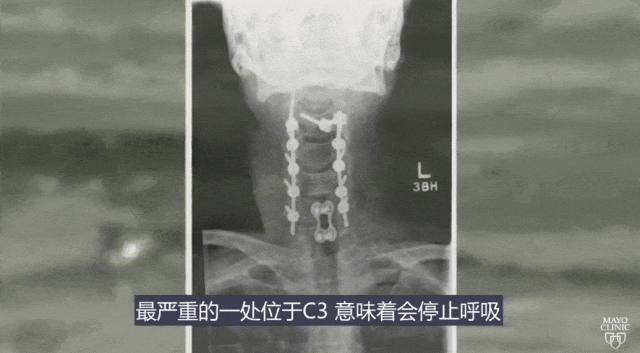

突然一个浪打来,克里斯摔倒并一头扎进了海底,由于用力太足,导致他脖子被摔断了八处,最严重的一处位于C3,这意味着他可能会随时停止呼吸。